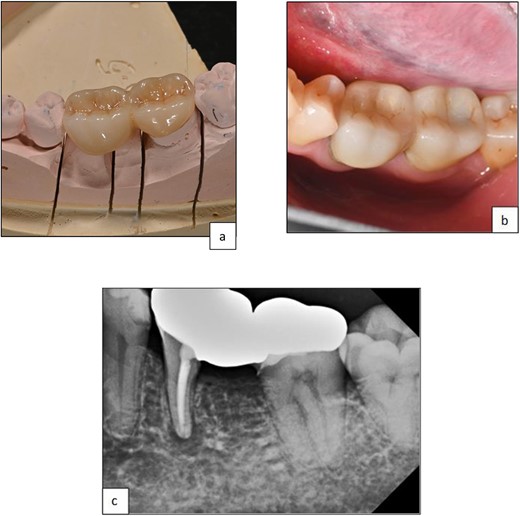

Follow-up at three months showed no symptoms, tenderness to percussion, swelling, periodontal pocketing, or mobility. This aligns with evidence suggesting that periodontal tissue maturation occurs within three months post-surgery [8]. Subsequently, tooth 35 and the distal segment of tooth 36 were prepared for a milled PFM bridge in preparation for upper and lower cobalt-chrome partial dentures. The design included a premolar pontic, a mesial rest seat on tooth 35, and a lingual rest seat on both teeth 35 and 36 (Fig. 11 and 12).

Clinical photographs showing the occlusal view of milled PBM bridge 35-P-36 after cementation.

Periapical radiograph post-cementation of bridge 35–36 showing good adaptation of restorative margins and healing of bony lesion.